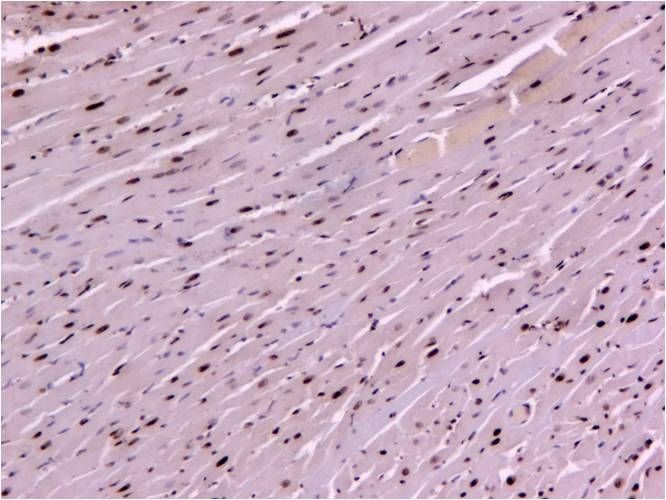

TUNEL染色是檢測細(xì)胞凋亡染色的常見方法,其原理是細(xì)胞在發(fā)生凋亡時,會激活一些DNA內(nèi)切酶,這些內(nèi)切酶會切斷核小體間的基因組DNA。細(xì)胞凋亡時抽提DNA進(jìn)行電泳檢測,可以發(fā)現(xiàn)180~200bp的DNA ladder?;蚪MDNA斷裂時,暴露的3'-OH可以在末端脫氧核苷酸轉(zhuǎn)移酶(Terminal Deoxynucleotidyl Transferase, TdT) 的催化下加上熒光素、生物素標(biāo)記的dUTP,從而可以通過熒光顯微鏡或化學(xué)顯色方法檢測細(xì)胞凋亡的情況。

可結(jié)合凋亡細(xì)胞形態(tài)特征來綜合判斷(未染色細(xì)胞變小、胞膜完整但出現(xiàn)發(fā)泡現(xiàn)象;晚期出現(xiàn)凋亡小體,貼壁細(xì)胞出現(xiàn)鄒縮、變圓、脫落;而染色細(xì)胞呈現(xiàn)染色質(zhì)濃縮、邊緣化、核膜裂解,染色質(zhì)分割成塊狀/凋亡小體)